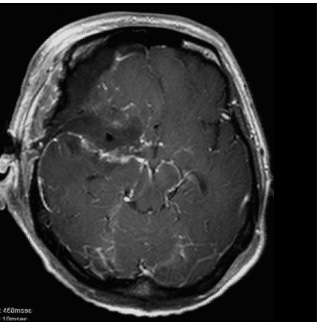

図2 頭蓋底髄膜腫 48歳女性 歩行障害、嚥下困難で来院

術後MRI:海綿静脈洞への浸潤部を除き

摘出、歩行障害改善し退院